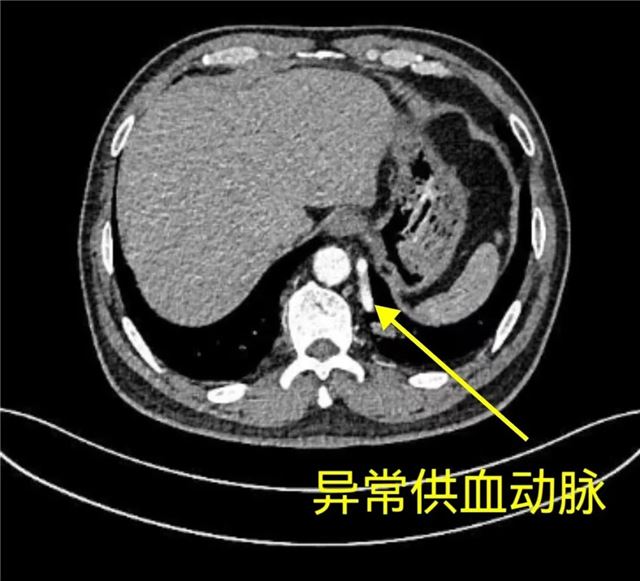

Q 什么是肺隔离症? 肺隔离症临床上较为少见,是一种先天性的肺部发育畸形。这种畸形表现为异常体循环动脉供血替代了肺动脉供血的部分肺组织,常发生于两肺下叶后基底段,紧邻膈肌或脊柱,且左侧较右侧更为常见。肺隔离症分为叶内型和叶外型,这部分肺组织与正常肺组织出现隔离,没有呼吸功能。由于长期的炎症刺激,它会形成囊性肿块,与正常的气管支气管树没有直接联系,但可能与支气管相通并导致反复感染。 肺隔离症的临床表现 叶内型隔离肺和正常肺支气管相通,可导致隔离肺的反复慢性感染。临床上,患者可出现咳嗽、咳痰、胸痛、咳血、发热等症状。然而,由于其临床症状多样化且缺乏特异性,常被临床医生忽视,因此较易误诊为支气管扩张、肺囊肿、慢性肺脓肿,甚至肺癌等。 叶外型单独包裹在其自身的异常胸膜下,与正常肺相对独立,通常无症状。但50%的叶外型肺隔离症患者可合并其他畸形,如膈疝、心血管畸形、肺发育不全、脊柱畸形、食管畸形等。 Q 如何诊断肺隔离症? 胸部增强CT和肺动脉血管造影检查是诊断肺隔离症的主要方法。 Q 如何治疗肺隔离症? 手术切除病变肺组织是主要的治疗手段,尤其是当病变肺组织感染难以控制、反复发作、长期迁延不愈时,应及时采取手术治疗。手术可以通过开胸手术或胸腔镜手术进行。目前我科主要行胸腔镜下肺叶切除或局部隔离肺切除,通过微创手术解决疾患的同时,实现术后快速康复。 专家提醒 肺隔离症患者病情隐匿,临床表现无特异性,容易并发反复的呼吸道感染,引起咳嗽、咳脓痰、发热、胸闷及呼吸困难等症状,因此容易漏诊及误诊。在临床工作中,对于长期反复肺部感染的患者,尤其是下肺存在病灶的患者,应提高警惕,尽早完善肺部CT、增强CT或血管成像等检查以明确诊断。一旦确诊肺隔离症,应根据患者的具体情况制定个性化的治疗方案,积极治疗,以改善患者的预后,减少并发症的发生,提高患者的生活质量。 划重点 肺隔离症的治疗关键在于早发现、早诊断、早治疗。 通过手术治疗,多数患者预后较好。由于临床上此病变较少见且容易误诊,手术风险较高,因此建议患者到胸外科专科就诊,让专科医生给出个体化的治疗或随访方案。肺部肿块并不直接等同于癌症,因此患者不必过于焦虑,应遵医嘱科学随访及治疗。 (文 / 胸外科 邢晋欣) 科室介绍:市级医学重点学科——胸外科 责编 | 李燕燕 初审 | 李向东 复审 | 李 鑫 终审 | 韩晓晶